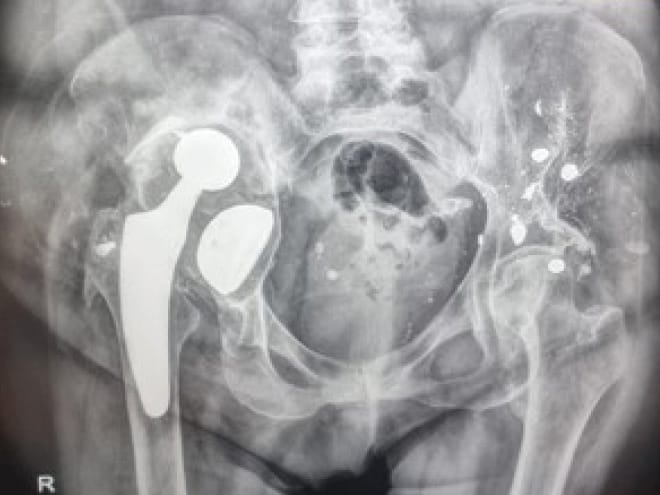

A classification system should accurately describe the problem, assist pre-operative evaluation and surgical pre-operative planning, and should predict outcomes. The recent Sen et al classification of late post-traumatic acetabular defects clearly reveals the patterns of post-traumatic nonunions and malunions.[1] Sen RK, Mukhopadhyay R, Pattanshetti V, Saini G, Tripathy SK, Sethy SS, Sharma SK. A New Classification System for Acetabular Bone Defect Evaluation in Posttraumatic Acetabular Nonunion and Malunion. Indian J Orthop. 2022 Jun 27;56(9):1601-1612 In the commonly used Paprosky classification, PD is often associated with IIIB and infrequently with IIC and IIIA bone defects.[4] Paprosky WG, Perona PG, Lawrence JM. Acetabular defect classification and surgical reconstruction in revision arthroplasty. A 6 year follow up evaluation. J Arthroplasty. 1994;9(1)33-34. However, the Paprosky classification fails to describe post-traumatic defects, and occasionally, orthopaedic surgeons encounter other acetabular bone defects which are not described by existing classification systems (Figure 1).

Conventional anteroposterior and lateral radiographs may initially be used for pre-operative planning for both post-traumatic and post-arthroplasty severe bone defects. PD should be suspected in cases with excessive osteolysis or fracture. When Kohler’s line and the tear drop is violated, and if moderate to severe ischial lysis is observed, and the cup and femoral head have migrated vertically more than 3 cm, one can safely suspect PD.[4], Paprosky WG, Perona PG, Lawrence JM. Acetabular defect classification and surgical reconstruction in revision arthroplasty. A 6 year follow up evaluation. J Arthroplasty. 1994;9(1)33-34.[5] Sporer SM, Paprosky WG. Acetabular revision using a trabecular metal acetabular component for severe acetabular bone loss associated with pelvic discontinuity. J Arthroplasty. 2006; 21(6)(S):87-90. However, the diagnosis of both post-traumatic malunion or nonunion and the diagnosis of PD in standard imaging views are difficult due to the fact that the implants obstruct full visibility of bone defects, especially when the posterior column is involved.[2], Schwarzkopf R, Ihn HE, Ries MD. Pelvic discontinuity: modern techniques and outcomes for treating pelvic disassociation. Hip Int. 2015; 25(4):368-74.[3] Babis GC, Nikolaou VS. Pelvic discontinuity: a challenge to overcome. EFORT Open Rev. 2021; 6(6):459-471. The use of a helical CT-scan and, more recently, the use of CT-scan thin slices in three planes, in combination with metal artifact reduction techniques, have improved diagnostic accuracy (Figure 2).[6], PuriL, Wixson RL, Stern SH, Kohli J, Hendrix RW, Stulberg SD. Use of helical computed tomography for the assessment of acetabular osteolysis after total hipa arthroplasty. J Bone J Joint Surg Am. 2002; 84(4):609-614.[7] Wellenberg RHH, Hakvoort ET, Slump CH, Boosma MF, MAAs M, Streekstra GJ. Metal artifact reduction techniques in musculoskeletal imaging. Eyr J Radiol. 2018; 107:60-69. Occasionally, a pre-operative CT angiogram is performed, when the removal of an intra-pelvic acetabular cup is planned. Despite technological improvements, one has to understand that resulting bone loss is usually greater than that which is initially anticipated during pre-operative planning.